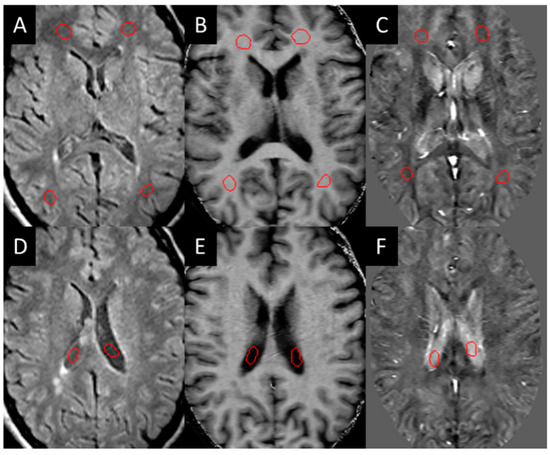

3.1. Lesions in MS Subjects